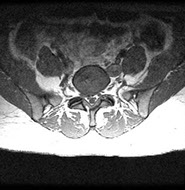

MRI (see image below)

Magnetic resonance image demonstrating extension of the nucleus pulposus to the right paracentral region of the spinal cord. The disc is adjacent to the inflamed right L5 nerve root. Courtesy of Barton Branstetter, MD.

MRI has demonstrated excellent sensitivity in the diagnosis of lumbar disc herniation and is considered the imaging study of choice for nerve root impingement. However, this preference is tempered by the prevalence of abnormal findings in asymptomatic subjects.